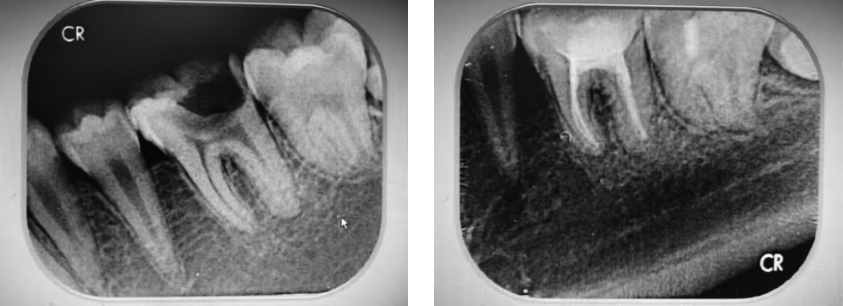

• 新型生物陶瓷iRoot SP联合单尖充填技术治疗慢性根尖周炎的临床效果

2025, 35(14):78-84. DOI: 10.3969/j.issn.1005-8982.2025.14.014

摘要 (283) HTML (310) PDF 769.00 K (95) 评论 (0) 收藏

摘要:目的 比较AH-Plus根管封闭剂结合热牙胶垂直加压充填技术与新型生物陶瓷iRoot SP联合单尖充填技术在慢性根尖周炎治疗中的临床效果。方法 选取2020年5月—2023年5月宝鸡市人民医院口腔科收治的慢性根尖周炎患者76例,按照随机数字表法分为对照组、观察组,各38例。对照组采用AH-Plus根管封闭剂结合热牙胶垂直加压充填技术,观察组采用新型生物陶瓷iRoot SP联合单尖充填技术。分别收集患者治疗前(T0)、治疗3个月(T1)、治疗6个月(T2)的龈沟液检测炎症因子水平。统计并比较两组患者根管充填时间、治疗充填质量与疗效。采用视觉模拟评分法(VAS)评估患者治疗各时期疼痛情况。统计两组患者治疗各时期咀嚼功能、咬合功能,采用电测牙髓试验(EPT)评估牙髓活性。采用根尖周指数(PAI)对患者X射线检查进行病损评估。结果 对照组充填时间长于观察组(P <0.05),超填比例高于观察组(P <0.05),显效/有效占比低于观察组(P <0.05)。观察组与对照组T1、T2时VAS评分比较,结果 ①不同时间点VAS评分比较,差异有统计学意义(P <0.05);②观察组与对照组VAS评分比较,差异有统计学意义(P <0.05);③两组VAS评分变化趋势比较,差异无统计学意义(P >0.05)。观察组与对照组T0,T1、T2时IL-1β、IL-6、IL-8、TNF-α水平比较,结果 ①不同时间点IL-1β、IL-6、IL-8、TNF-α水平比较,差异均有统计学意义(P <0.05);②观察组与对照组IL-1β、IL-6、IL-8、TNF-α水平比较,差异均有统计学意义(P <0.05);③两组IL-1β、IL-6、IL-8、TNF-α水平变化趋势比较,差异均有统计学意义(P <0.05)。观察组与对照组T0、T1、T2时EPT、咀嚼功能、咬合功能评分比较,结果 ①不同时间点EPT、咀嚼功能、咬合功能评分比较,差异均有统计学意义(P <0.05);②观察组与对照组EPT、咀嚼功能、咬合功能评分比较,差异均有统计学意义(P <0.05);③两组EPT、咀嚼功能、咬合功能评分变化趋势比较,差异均有统计学意义(P <0.05)。观察组与对照组T0、T1、T2时PAI评分比较,结果 ①不同时间点PAI评分比较,差异有统计学意义(P <0.05);②观察组与对照组PAI评分比较,差异有统计学意义(P <0.05);③两组PAI评分变化趋势比较,差异无统计学意义(P >0.05)。结论 iRoot SP联合单尖充填技术治疗慢性根尖周炎能够显著缩短治疗时间,有效控制治疗后疼痛,并在根尖区病损治疗及充填质量上展现出更佳的效果。